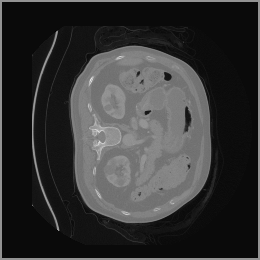

To demonstrate the advantages of 3D semantic image synthesis over 2D semantic semantic image synthesis, we conducted a detailed comparison with the SegGuidedDiff [26] model. SegGuidedDiff generates medical images based on 2D semantic maps, producing individual 2D slices that are later stacked to form a 3D image. However, this approach has limitations in capturing spatial continuity and coherence across slices, which is critical for representing the spatial structure of 3D medical images. As a result, inconsistencies often arise between different slices, particularly in preserving anatomical structures across the coronal and sagittal planes. The generated images exhibit varying levels of denoising, resulting in differences in brightness and sharpness across the images. This inconsistency in denoising can lead to noticeable variations in visual quality, where some regions appear clearer and others less distinct.

As shown in Figure 5, the generated slices exhibit high consistency across adjacent slices. The anatomical structures and semantic patterns are smoothly and coherently preserved between slices, indicating that our model is capable of generating 3D-consistent synthetic images rather than isolated 2D slices.

In contrast, the segmentation result of synthetic data generated by SegGuidedDiff using 2D semantic map slices shows significantly lower performance (Dice = 0.602). Notably, SegGuidedDiff generates images slice-by-slice in 2D without modeling the full 3D spatial context. As a result, the synthesized volumes often suffer from inter-slice inconsistencies and unrealistic spatial structures, which negatively impact the downstream segmentation performance.

Figure 8 further supports these findings: the images generated by Med-LSDM preserve spatial coherence across coronal and sagittal planes, whereas those from SegGuidedDiff show noticeable inconsistencies. These artifacts likely result from the 2D nature of SegGuidedDiff, which fails to account for 3D spatial relationships. In contrast, our model’s volumetric diffusion framework inherently preserves anatomical consistency, highlighting its advanta in synthesizing high-fidelity 3D medical images.